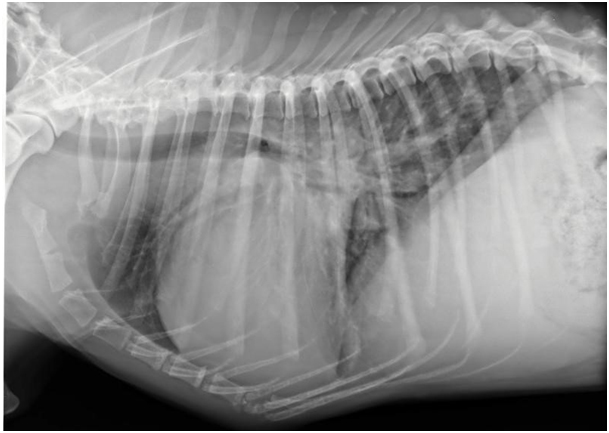

Die Krankheit „Dilatative Cardio Myopathie“ hat sich bereits vor vielen Jahren geäußert bei unserem Dobermann. Als ein Dobermann plötzlich starb wurde damals oft gesprochen von „Sudden Death“. Ebenfalls konnten Tierärzte mit klinischer Untersuchung, Röntgenbild und Elektrokardiogram Herzversagen bestätigen beim Dobermann mit reduzierter Kondition. Mit mikroskopischer Untersuchung konnte man Narbe Gewebe zwischen noch gesunde Herzmuskelzellen feststellen.

Röntgenbild vom Dobermann mit vergrößertem Herz und Wasser in der Lunge

Mitte der 90er Jahre wurde mittels besserer Herzultraschallgeräte immer mehr bekannt über den DCM- Krankheitsprozess. Im Prinzip erweitert sich langsam aber sicher die linke Herzwand und im nach hinein auch das Septum zwischen linker und rechter Herzkammer. Somit tritt Leckage der linken Herzklappe auf und erweitert dadurch auch den linken Vorhof. Dies führt zu einer Störung der elektrischen Übertragung in der Vorhofwand, wodurch Herzrhythmusstörungen auftreten können.